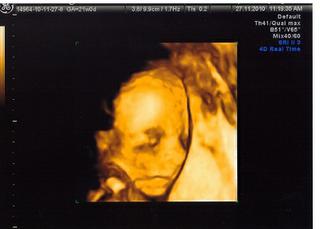

Baby ktore ste uz mali sono, kolko teraz uz meria babatko?

@23lenka - ano chceme aj na 3D - tak do mesiaca. zajtra sa chcem objednat. cena tusim zacina od £90, ale to je len za fotky a potom sa to splha az do vyse 200 - podla toho co si chces odniest. my chceme len zopar fotiek a dvd, tak asi okolo £150. je to dost, ale pri prvom som nebola a teraz si to dame 'pod stromcek'. 🙂

u nas v Kosiciach v Procare nemocnici pytaju za 4D ultrazvuk + DVD k tomu 55 Eur.

@smajka no je to dost nie ....aj u nas stoji 195£...a to je k tomu 15min dvd aj s hudbou 10 foto vo formate A5....a to vsetko je 195£ oni uz nevedia kolko za to pytat...a keby som bola bola na tej klinike zaregistrovana mam to vsetko za 100£ pekne nie?My este s mojim rozmyslame ci ist ci ee....no a dufam ze potom das nejake fotecky....a tam ti aj pohlavie povedia to bude super nie?